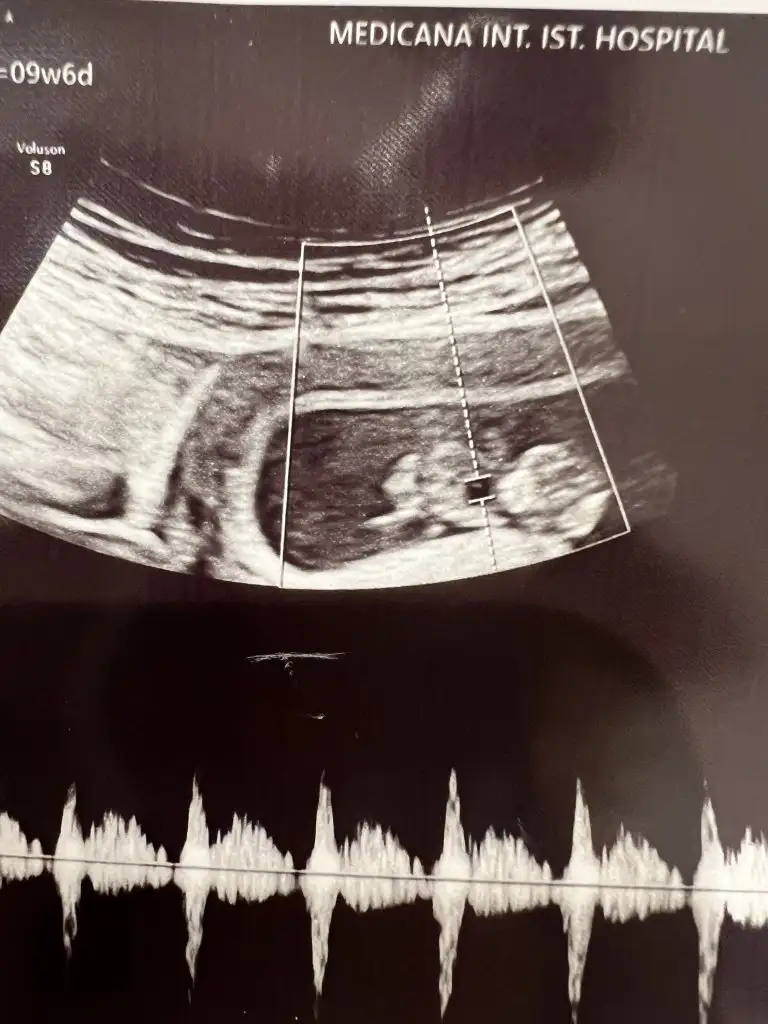

Evet baya ya kendi doktorum son kontrolde ense kalınlığı iyi 1,4 dedi bu doktor beni sinir ettiEvet yaa o testler insan uzmece bende 2 gun uzuldum sonra tooparladim simdi fetali bekliyorum.araya bayram girdi yasin kac senin canim

Testin guzel cikar o testlere gerek yokta istiyorlar perinataloglarda para kazanmasi lazim biraz yipratmaca uzmeceEvet baya ya kendi doktorum son kontrolde ense kalınlığı iyi 1,4 dedi bu doktor beni sinir etti30 yaşındayım canım ben